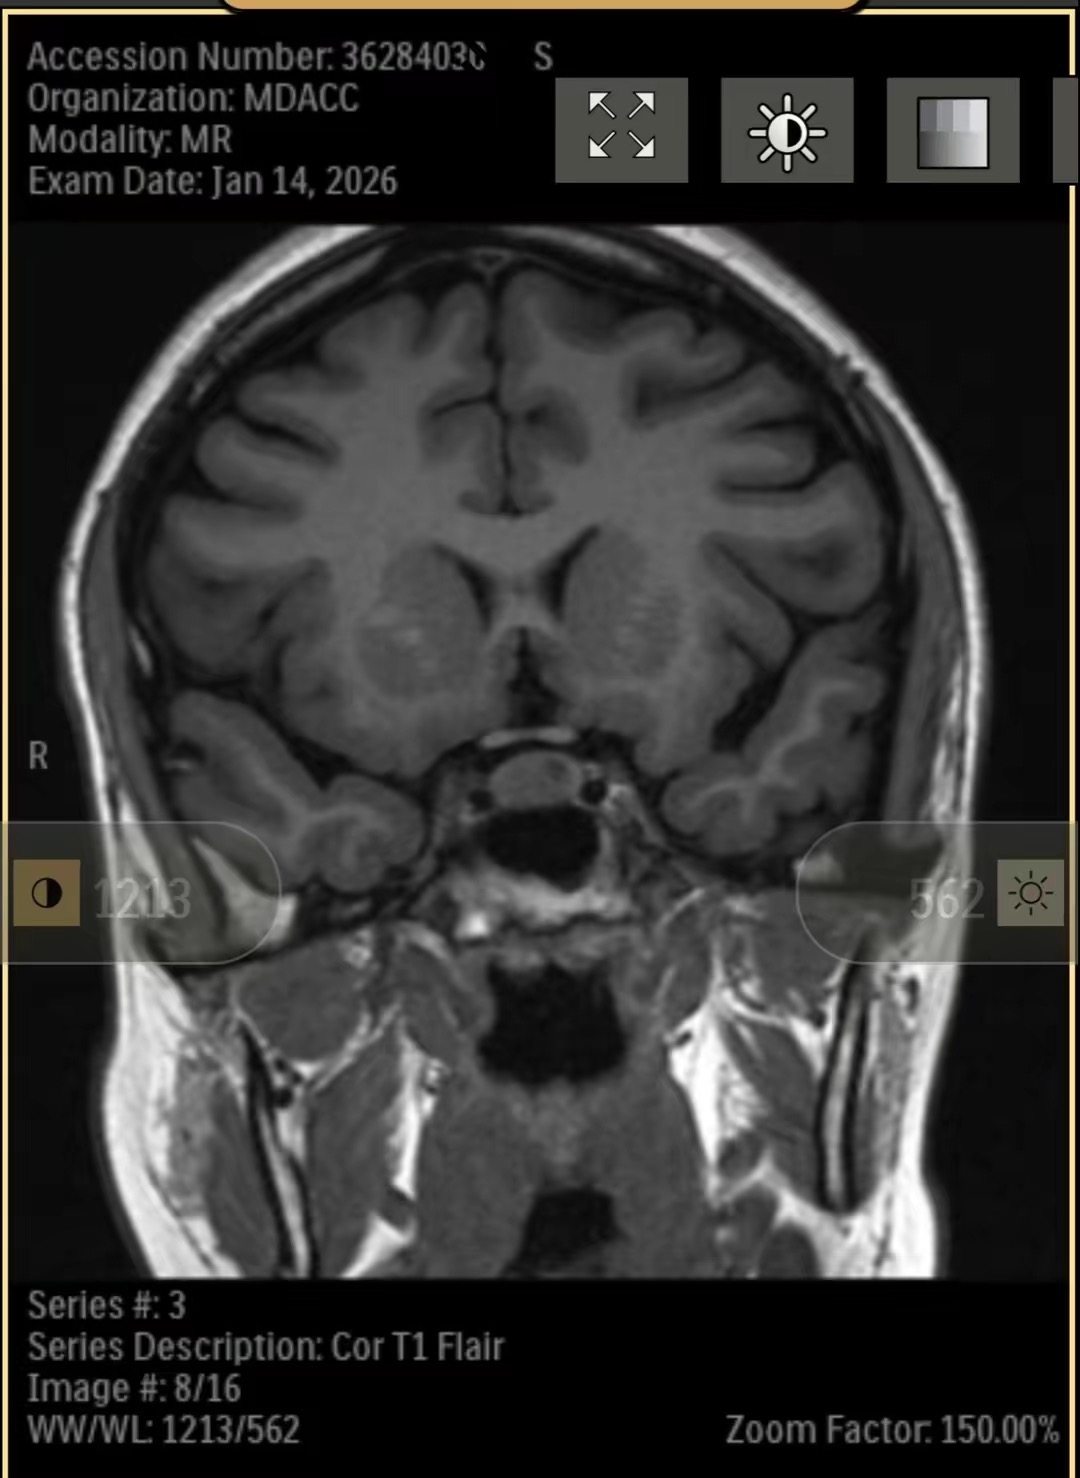

Recently, I was diagnosed with a pituitary brain tumor. Since then, my life—and my family’s—has changed in ways we couldn’t have prepared for. Between medical appointments, testing, treatment planning, and travel for specialized care, the financial and emotional weight has become heavy very quickly.